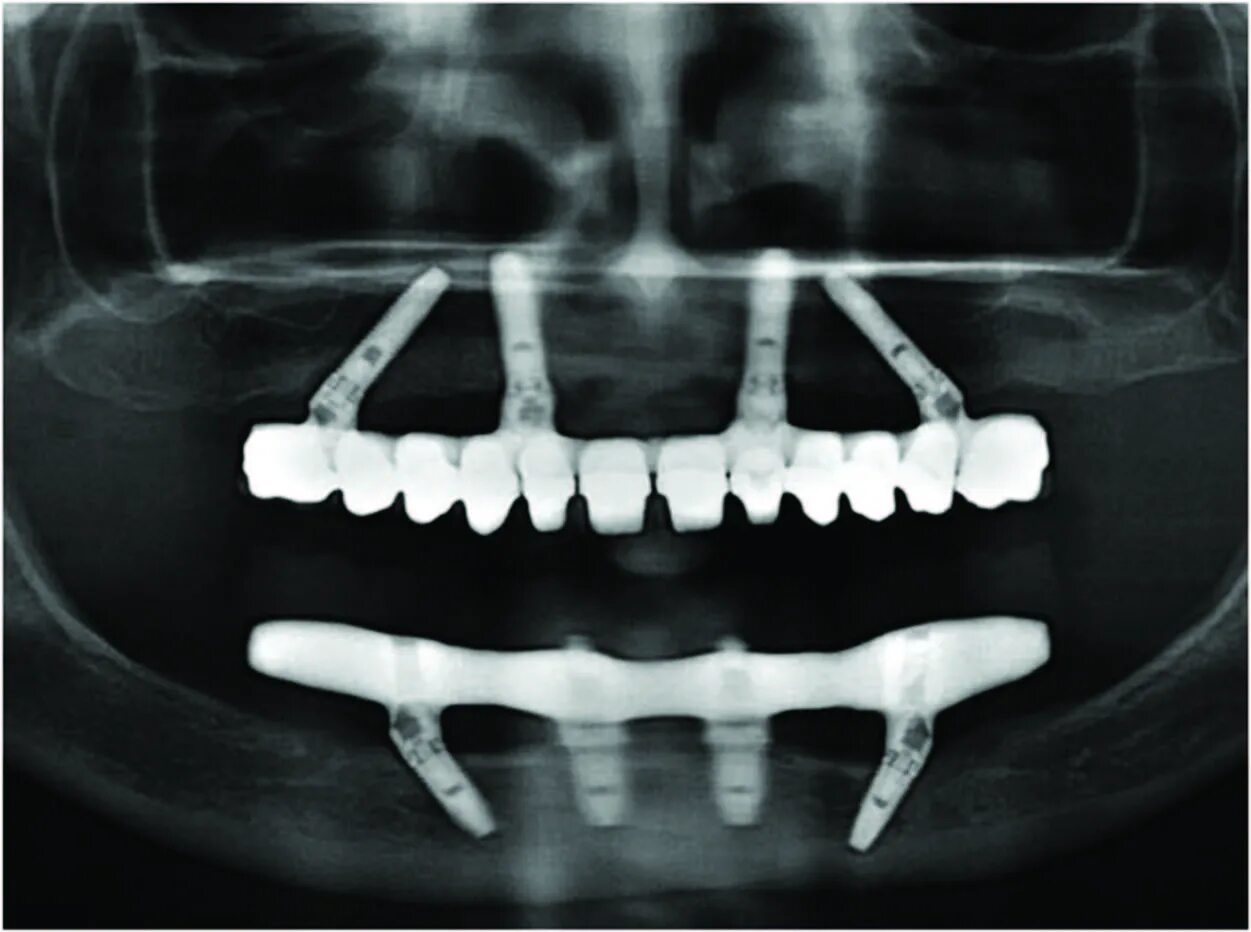

Ол он 4